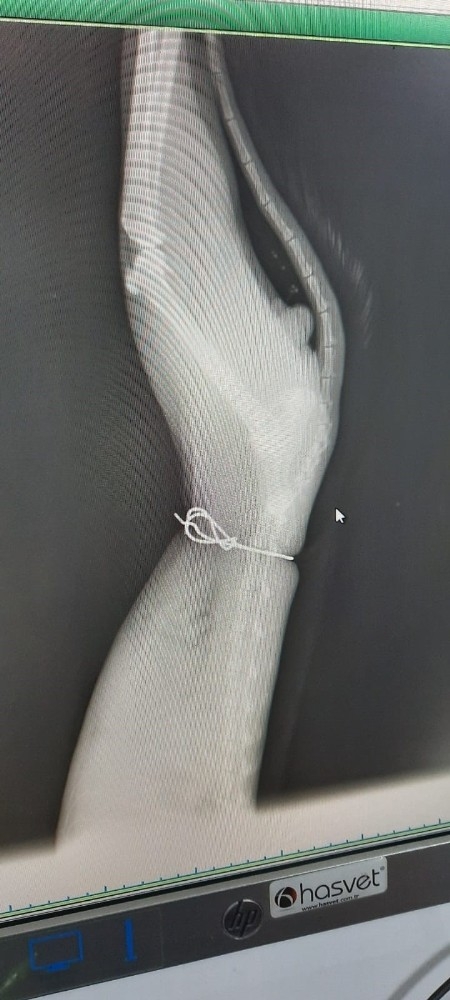

Yapılan muayenede bir bulguya rastlanmazken korkunç olay çekilen röntgende ortaya çıktı. Röntgende kedinin karnına sarılıp düğümlenmiş bir çelik tel olduğunu fark eden Veteriner Hekim Muhammed Coduroğlu, büyük şaşkınlık yaşadı. Kedinin tüylerinin altında kaldığı için dışarıdan fark edilmeyen teli kesen Veteriner Hekim Coduroğlu, hayvanı klinikte gözetim altına aldı.

Kedinin boğazına düşkün olduğunu belirten Salih Aran, "Kediyi 3 yıldır bahçemizde besliyoruz. Son zamanlarda epey zayıflamıştı. Verdiğimiz şeyi doğru düzgün yiyemiyordu. Yediği zaman kusuyordu. Tuvaletini yapamıyordu. İnsanlardan kaçıyordu. Bunları fark edince bağırsaklarında bir sorun olduğunu düşünerek Veteriner Hekim Muhammed Coduroğlu'na götürdüm. Fiziki muayenede bir şey yoktu. Ancak röntgeni gördüğümüzde şok olduk. Vicdansız birisi çelik telle hayvanın karnını sıkarak bağlamış. Bu nedenle doğru beslenme ve sindirim yapamamış" dedi.

Önce kedinin bir tel parçasına takılmış olabileceğini düşündüğünü belirten Salih Aran, "Kedinin karnına sarılan tel sıkıca gerdirilip alttan pense ile düğümlenmiş. Konuşamayan, derdini anlatamayan bir hayvana bu insafsızlığı kim yapar bilmiyorum. Kedimiz şimdi veteriner arkadaşımız tarafından müşahede altına alındı. Karnı telle sıkıştırıldığı için bağırsakları yapışmış. İyileşmezse ameliyat edilecek" diye konuştu.